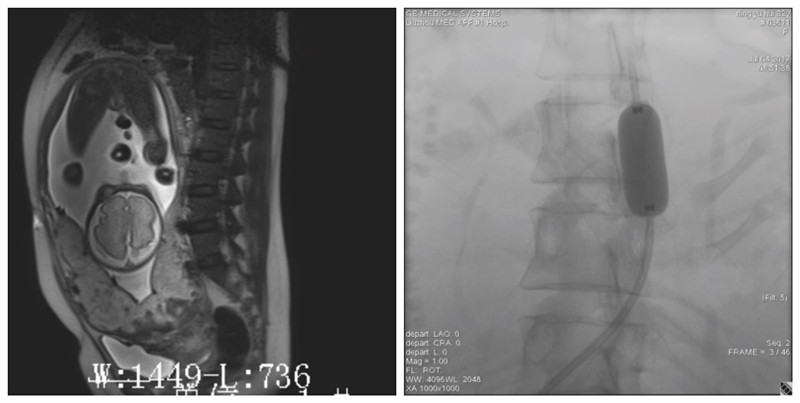

凶险性前置胎盘剖宫产术前腹主动脉远端球囊预置术

腹主动脉远端球囊预置

凶险型前置胎盘是指既往有剖宫产史或子宫肌瘤剔除术史,此次妊娠28周以后,胎盘附着在子宫下段前壁,下缘达到或覆盖宫颈内口,发生胎盘粘连、植入和致命性大出血的风险高,称之为凶险型前置胎盘。凶险型前置胎盘可在短时间内导致产科严重出血,手术难度大,剖宫产子宫切除几率以及其他手术并发症包括膀胱、输尿管损伤,输尿管瘘或肠管损伤等明显升高。同时,由于大量反复输血造成的急性肺损伤、凝血功能异常等并发症显著增加了孕产妇死亡率。目前,在凶险性前置胎盘剖宫产术中为控制出血,比较理想的方法是根据情况术前行腹主动脉远端球囊预置术,待胎儿娩出后,扩张球囊可减少术中短时间内大量出血,保持血流动力学稳定,为治疗赢取时间,为保留子宫创造条件。

我院产科自2017年开展凶险型前置胎盘剖宫产术前腹主动脉远端球囊预置阻塞术以来,已经成功挽救了二十余例年轻产妇的子宫,也挽救了这些产妇的家庭,是柳州市最早开展该项技术的医院之一。